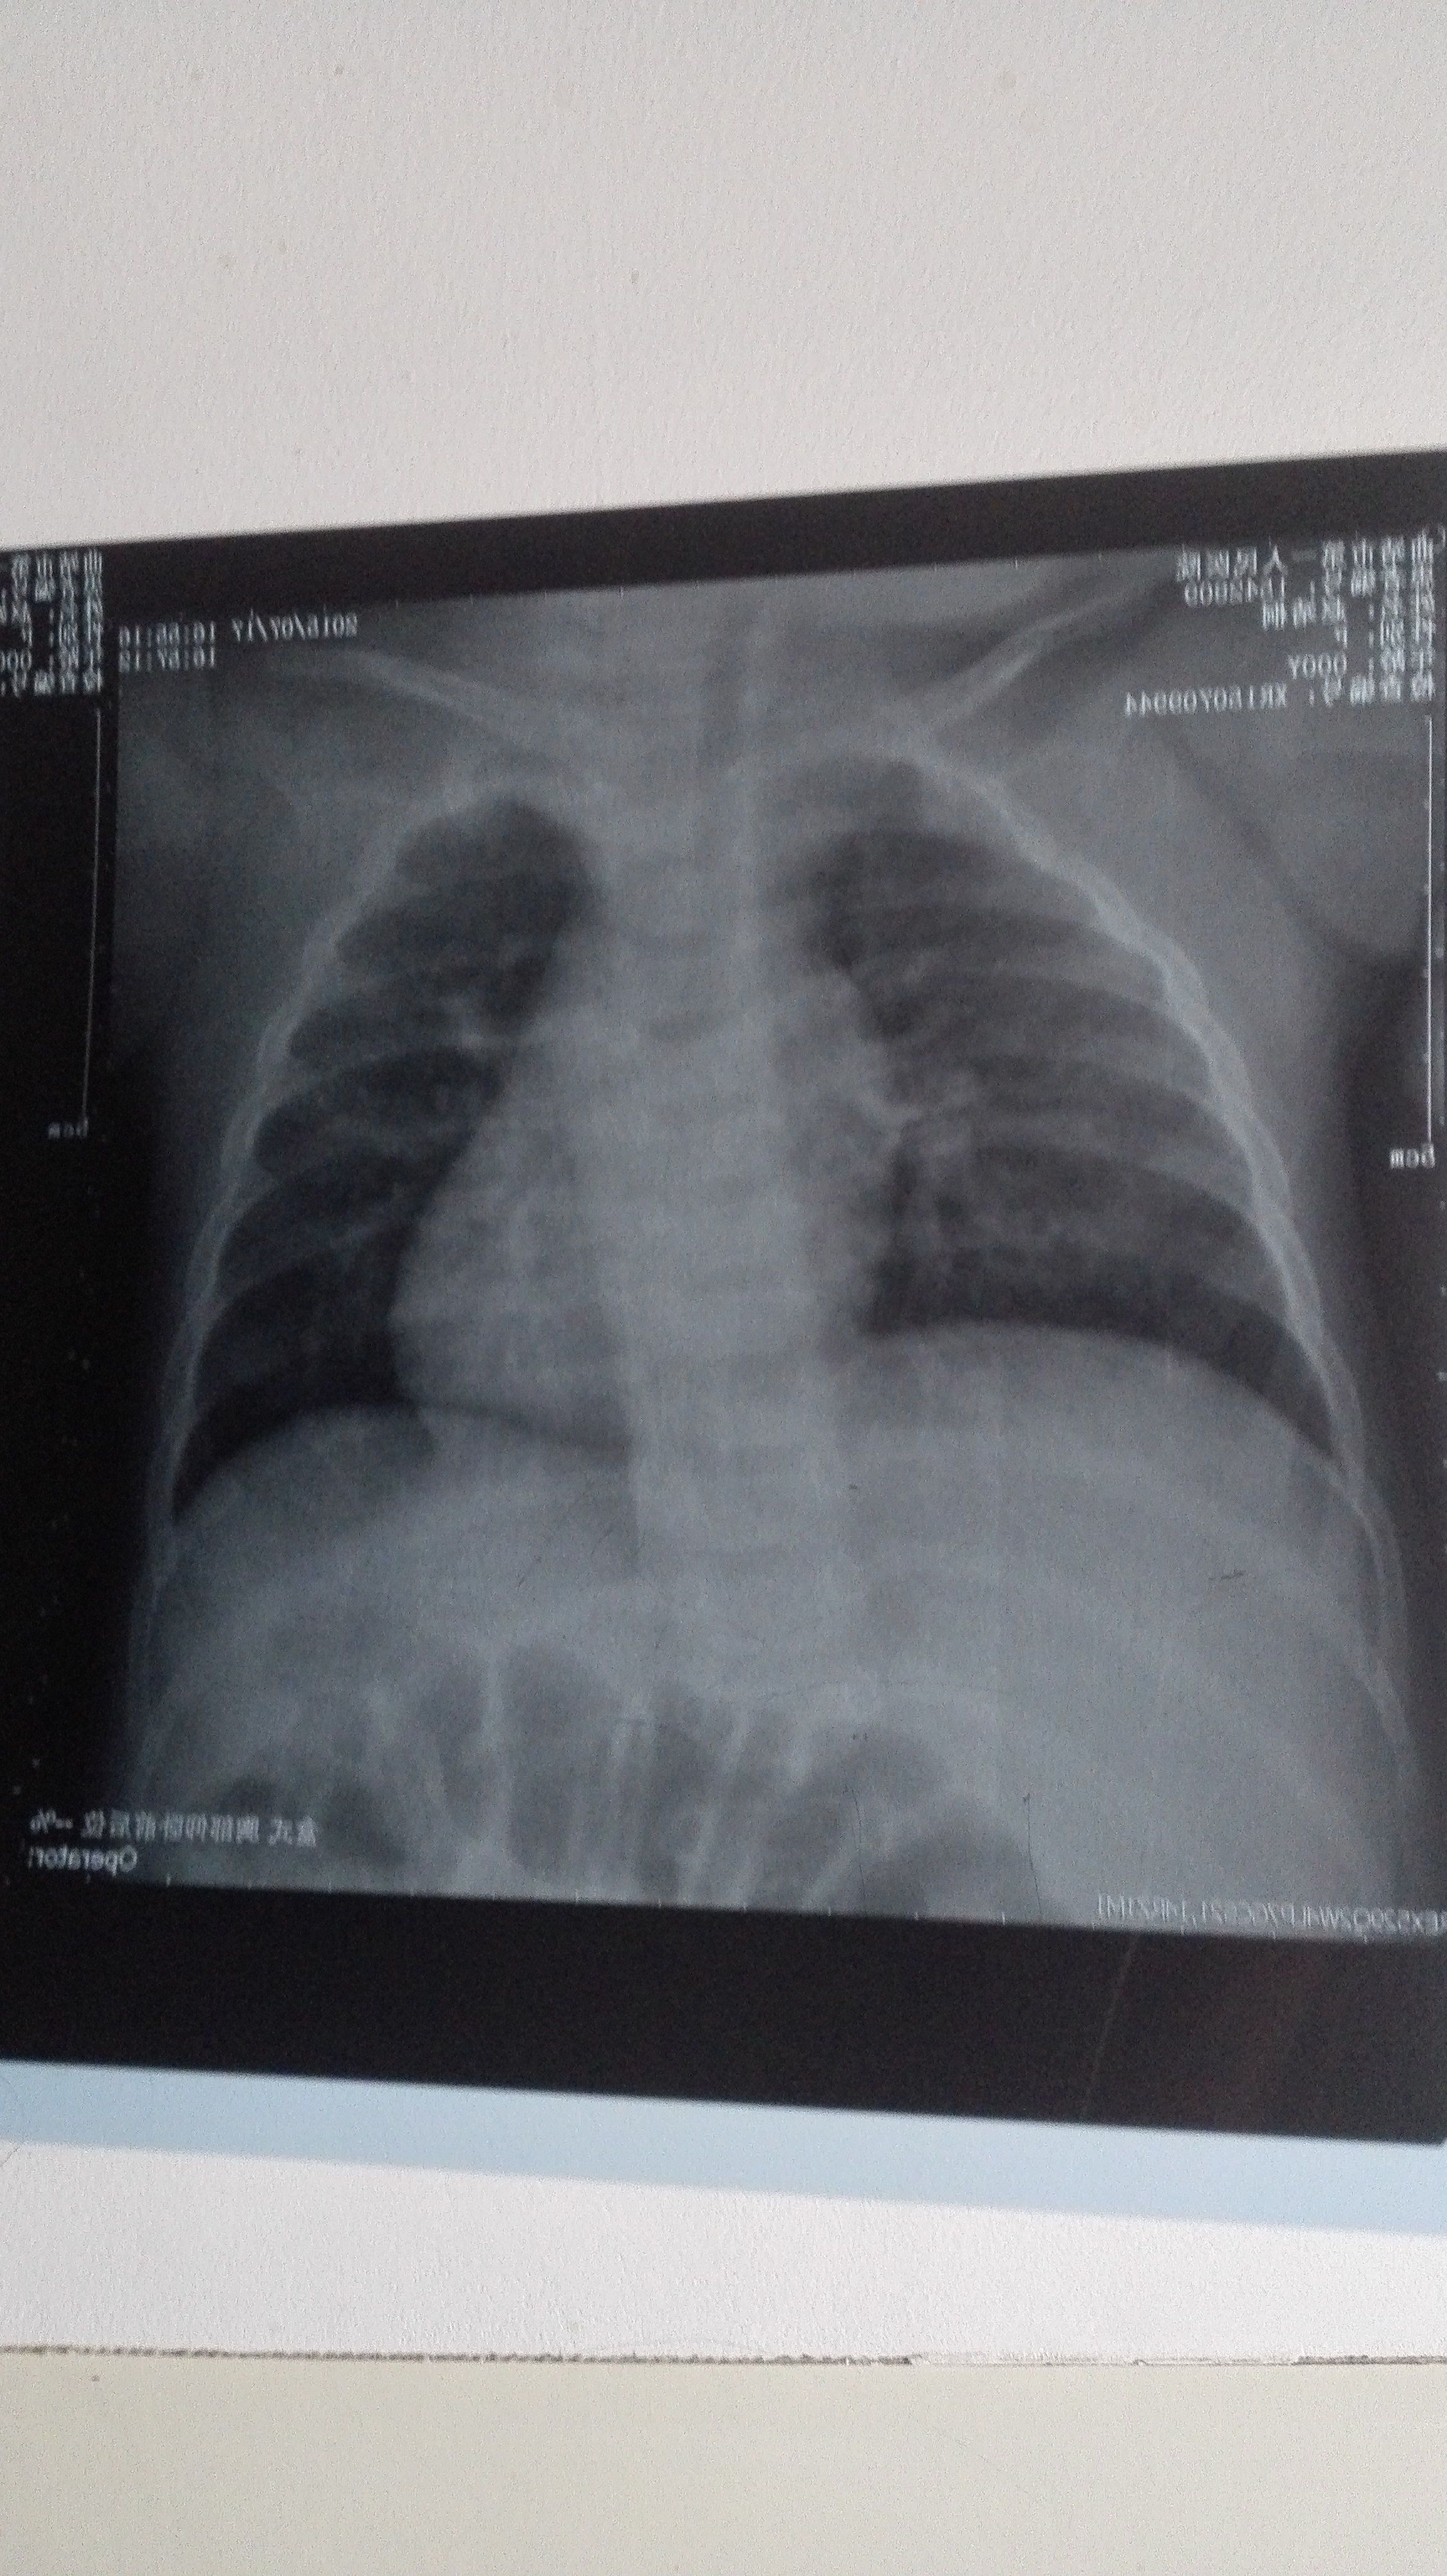

半岁婴儿胸片图,是不是肺炎 前几天发热,医生说看不出来,还要照CT,可怜的娃娃 点击展开 匿名用户 2015-07-18 20:44 满意回答 你好!从图片看,多是考虑有支气管炎的可能稼团洞!至于到肺炎的那种程度!还没有浅迷呢!可柴葵以根据血常规,来采用治疗方法 ˲88996 2015-07-18 20:57 宝宝知道提示您:回答为网友贡献,仅供参考。 相关问题 小孩一岁半了肺炎发热咳嗽做个CT说是两肺上都有炎正现住院输液一个多月了不见好急死人了,另外输液期间… 1月2号末次月经1月9号女儿肺炎拍了胸片我进去把着她因为还小怀孕了宝宝有事吗 胸闷胸病,照胸片 胸部CT 心电图查不出病因